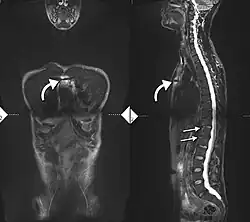

If these criteria still do not give a compelling diagnosis magnetic resonance imaging (MRI) may be useful.[22][24] MRI can show inflammation of the sacroiliac joint.

The earliest changes demonstrable by plain X-ray shows erosions and sclerosis in sacroiliac joints. Progression of the erosions leads to widening of the joint space and bony sclerosis. X-ray spine can reveal squaring of vertebrae with bony spur formation called syndesmophyte. This causes the bamboo spine appearance. A drawback of X-ray diagnosis is the signs and symptoms of AS have usually been established as long as 7–10 years prior to X-ray-evident changes occurring on a plain film X-ray, which means a delay of as long as 10 years before adequate therapies can be introduced.[25]

Options for earlier diagnosis are tomography and MRI of the sacroiliac joints, but the reliability of these tests is still unclear.

T1-weighted MRI with fat suppression after administration of gadolinium contrast showing sacroiliitis in a person with ankylosing spondylitis

T1-weighted MRI with fat suppression after administration of gadolinium contrast showing sacroiliitis in a person with ankylosing spondylitis